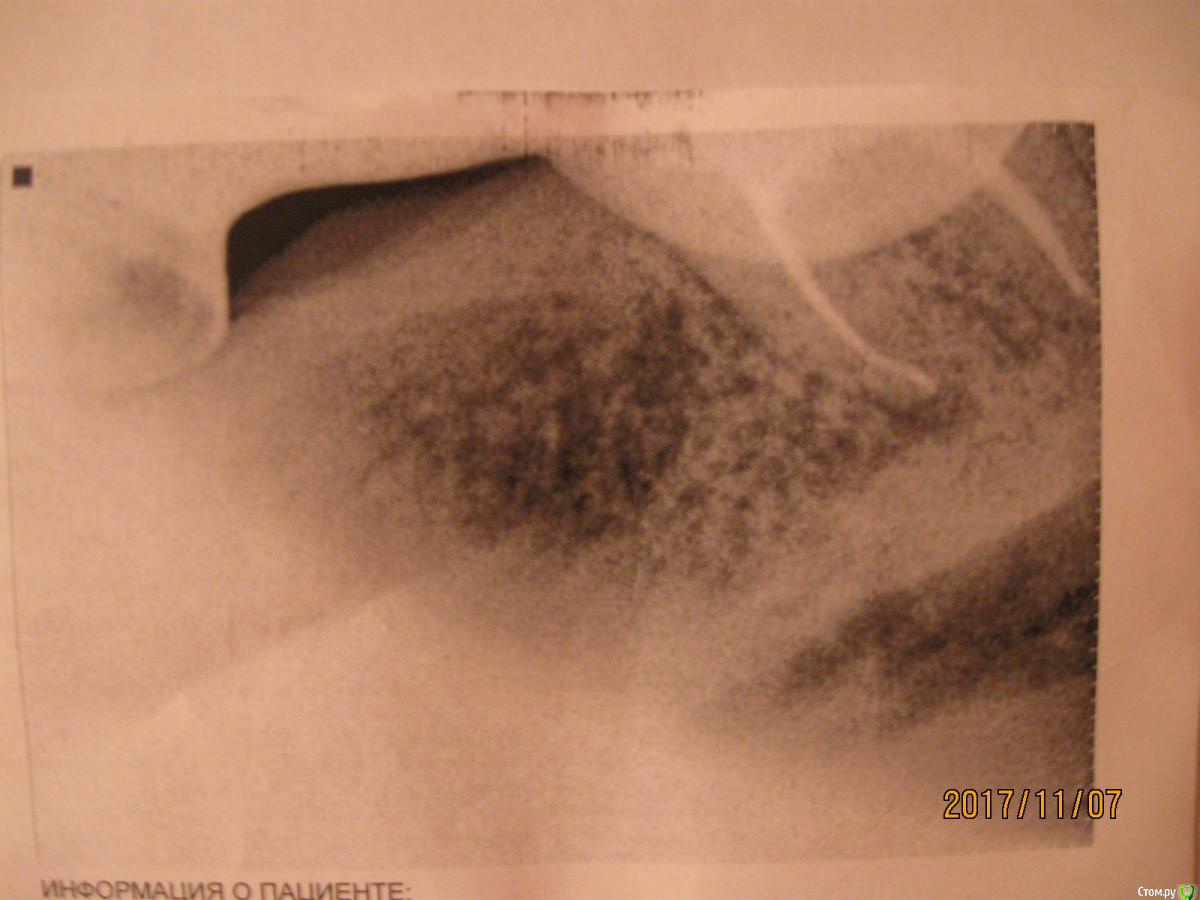

meld Опубликовано 7 ноября, 2017 Автор Поделиться Опубликовано 7 ноября, 2017 Прицельный снимок 38 зуба и его срезы Ссылка на комментарий